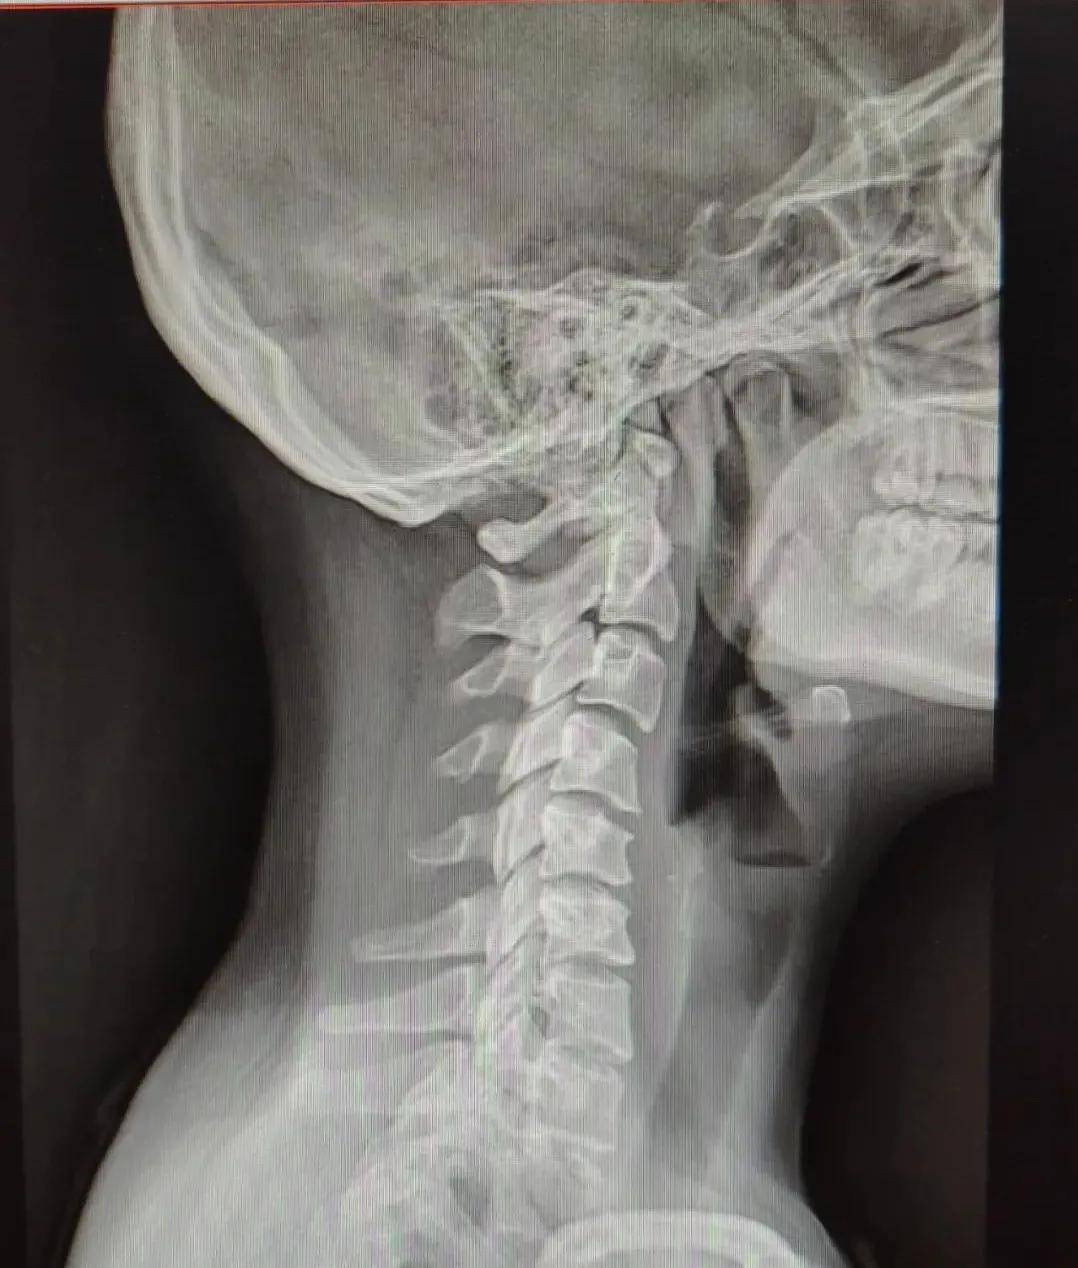

DR检查

DR , 即数字X线成像检查 , 是人体不同组织对X射线的吸收程度 , 呈现不同灰度的图像 。 对软组织的成像效果较差 , 比如肌肉、神经、椎间盘等 , 因此某些情况下不能满足椎间盘疾病诊断的需要 。 但其可以清楚的观察脊柱骨骼边界、大小、形态 , 尤其是对脊柱整体骨性结构的显示较好 , 能够发现脊柱退行性改变及结构的异常 , 如脊柱侧弯 , 生理曲度改变等 , 并可发现其他一些脊柱疾患 , 如滑脱、结核、肿瘤等 。

文章图片

颈椎生理曲度反曲